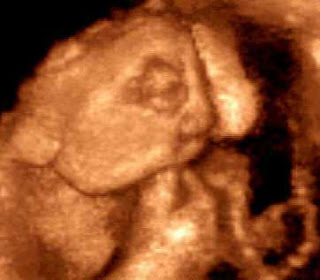

Um pedido para realização de aborto chegou à Vara da Infância e Juventude de Macapá. A solicitação foi motivada depois que a autora, ainda menor de idade e não estando regularmente assistida pelos pais, ter sido orientada para a interrupção da gestação depois que exames constataram ser o feto portador de anencefalia (ausência de cérebro).

Sobre a pretensão do ato, o Magistrado deu importância à manutenção da vida do feto, salientando não existir perigo real de vida para a gestante, e afirmou: “optarei sempre pela vida, porque, muito embora indeterminado o momento do óbito, nem por isso deixará de ser vida humana”.